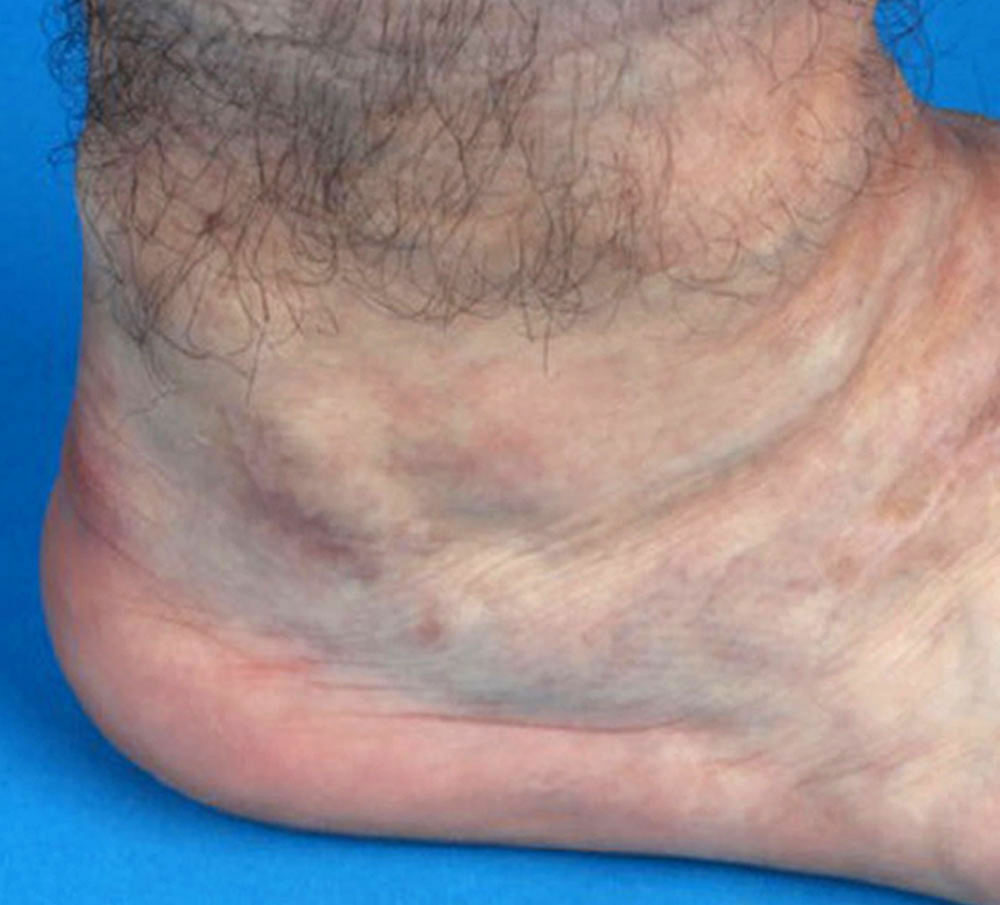

Patients with venous malformations, in particular, have a significantly increased tendency to develop phlebothrombosis and thrombophlebitis. In these patients, the vein walls are pathologically altered, the veins themselves are often markedly dilated, and the blood flow velocity is greatly reduced. If there are connections from the venous malformation to the body's draining truncal venous system via communicating or drainage veins, the risk of thromboembolism is substantially increased. This can pose a significant risk to patients in their long-term course.

In thrombophlebitis, on the other hand, this blood clot formation is more circumscribed and usually affects smaller veins, mainly those located superficially under the skin or within a venous malformation. In this situation there may not be a direct connection to the deep, draining vein system. Thus, a blood clot usually cannot reach the right heart and pulmonary arteries. There is also no relevant congestion of the outflowing venous blood.

The thrombi formed in the veins or venous malformation are finally cleared via an aseptic inflammatory reaction and degradation. This is painful and a common cause of recurrent local symptoms in patients with venous malformations.